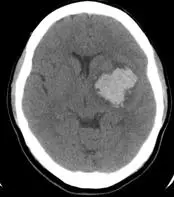

下圖為56 歲女性之電腦斷層影像,平時有高血壓,突然發生半身無力,意識障礙,則最正確的診斷為下列何者? 圖片

本題 CT 影像為非對比軸切面腦部電腦斷層,可見以下特徵:

• 高密度病灶(hyperdense lesion):右側大腦半球深部可見一橢圓形、均質性高密度病灶,密度約為 50–70 HU,符合急性出血表現(新鮮血液在 NCCT 呈高密度白色,因血紅蛋白中的血球蛋白及凝血因子對 X 射線有較高吸收率)

• 病灶位置:位於右側基底核區(basal ganglia),對應殼核(putamen)位置,屬於腦深部中央型出血,與高血壓性腦出血典型分布一致

• 病灶形態:邊界相對清晰,呈均質高密度,無明顯「爆米花」狀(popcorn appearance)或環形強化跡象

• 無蜘蛛網膜下腔出血特徵:腦底池(basal cisterns)及腦溝(sulci)並無瀰漫性高密度,不符合蜘蛛網膜下腔出血典型 CT 圖像(星形/五角形分布於鞍上池周圍)

• 周邊水腫:病灶周邊可見輕微低密度水腫帶(hypodense rim),符合急性腦內出